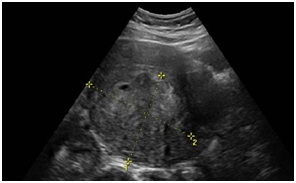

High Grade Primary Intratesticular Leiomyosarcoma: A Very Rare Presentation

Journal of Oncology Research and Therapy